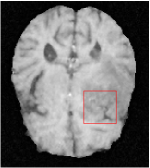

All the experiments are implemented on a Windows workstation with Intel Core i9 CPU at 3.3GHz and an Nvidia GTX-1080Ti GPU with 11GB of graphics card memory via TensorFlow Abadi et al. (2016). The parameters in the proposed network are initialized by using Xavier initialization Glorot and Bengio (2010). We trained the meta-learning network with four tasks synergistically associated with four different CS ratios: 10%, 20%, 30%, and 40%, and test the well-trained model on the testing dataset with the same masks of these four ratios. We have 300 training data for each CS ratio, which amount to total of 1200 images in the training dataset. The results for and MR reconstructions are shown in Tables 5.4 and 5.4 respectively. The associated reconstructed images are displayed in Figures 1 and 3. We also test the well-trained meta-learning model on unseen tasks with radio masks for skewed ratios: 15%, 25%, 35%, and random Cartesian masks with ratios 10%, 20%, 30% and 40%. The task-specific parameter for the unseen tasks are retrained for different masks with different sampling ratios individually with fixed task-invariant parameters . In this experiments, we only need to learn for three skewed CS ratios with radio mask and four regular CS ratios with Cartesian masks. The experimental training proceed on less data and iterations, where we performed on 100 MR images with 50 epochs. For example, for reconstructing MR images with CS ratio 15% radio mask, we fix the parameter and retrain the task-specific parameter on 100 raw data with 50 epochs, then test with renewed on our testing data set with raw measurement that sampled from radio mask with CS ratio 15%. The results associated with radio masks are shown in Table 5.4 and 5.4, Figure 2 and 4 for and images respectively. The results associated with Cartesian masks are list in Table 5.4 and reconstructed images are displayed in Figure 5.

In general supervised learning, training data need to be in the same or similar distribution, heterogeneous data exhibits different structure variations of features which hinders CNNs to extract features efficiently. In our experiments, raw measurements sampled from different ratios of compressed sensing display different levels of incompleteness, these undersampled measurements do not fall in the same distribution but they are related. Different sampling masks are shown at the bottom of Figure 1 and 2 may have complemented sampled points, in the sense that some of the points which sampling ratio mask does not sample have been captured by other masks. In our experiment, different sampling masks provide their own information from their sampled points so that four reconstruction tasks help each other to achieve an efficient performance. Therefore, it explains the reason that Meta-learning is still superior to conventional learning when the sampling ratio is large.

In this section, we test the generalizability of the proposed model that tests on unseen tasks. We fix the well-trained task-invariant parameter and only train for sampling ratios 15%, 25% and 35% with radio masks and sampling ratios 10%, 20%, 30% and 40% with Cartesian masks. In this experiment, we only used 100 training data for each CS ratio and apply a total of 50 epochs. The averaged evaluation values and standard deviations are listed in Table 5.4 and 5.4 for reconstructed T1 and T2 brain images respectively that proceed with radio masks, and Table 5.4 shows the qualitative performance for reconstructed T2 brain image that applied random Cartesian sampling masks. In T1 image reconstruction results, meta-learning improved 1.6921 dB in PSNR for 15% CS ratio, 1.6608 dB for 25% CS ratio, and 0.5764 dB for 35% comparing to the conventional method, which in the tendency that the level of reconstruction quality for lower CS ratios improved more than higher CS ratios. A similar trend happens in T2 reconstruction results with different sampling masks. The qualitative comparisons are illustrated in Figure 2, 4 and 5 for T1 and T2 images tested in skewed CS ratios in radio masks, and T2 images tested in Cartesian masks with regular CS ratios respectively. In the experiments that conducted with radio masks, meta-learning is superior to conventional learning especially at CS ratio 15%, one can observe that the detailed region in red boxes keeps edges and is more close to the true image, while conventional method reconstructions are hazier and lost details in some complicated tissue. The point-wise error map also indicates that Meta-learning has the ability to suppress noises.